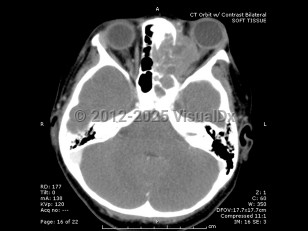

Orbital rhabdomyosarcoma - External and Internal Eye

Rhabdomyosarcoma is a rare childhood cancer that affects approximately 350 children per year in the United States, with 10% of cases involving the orbit. Rhabdomyosarcoma is the most common primary orbital tumor in childhood. Patients usually present between 5 and 10 years of age, with boys having a higher incidence than girls.

Orbital rhabdomyosarcoma develops from undifferentiated mesenchymal cells that have the capacity to become striated muscle. There are several histopathologic types, including embryonal (the most common form) and alveolar (which carries the worst prognosis).

Proptosis is the most common presenting sign and may develop over the course of just a few days or a month. Often there is a history of recent trauma upon presentation of the tumor, which may lead to confusion with the diagnosis. Orbital rhabdomyosarcoma sometimes presents with strabismus or as a localized eyelid or conjunctival mass.